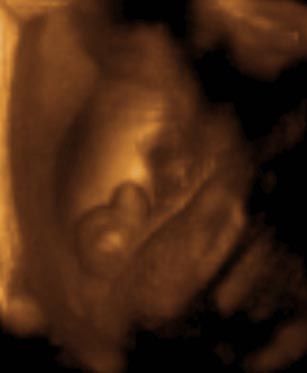

عکس جنین پسر در سونوگرافی سه بعدی هفته بیستم و هشتم بارداری

در سونوگرافی سه بعدی آلت تناسلی در بین پاها معلوم میشود. بهترین زمان انجام سونوگرافی سه بعدی میتواند هفته بیست و هشتم بارداری باشد.

در سونو سه بعدی شما میتوانید جنین خود را واضح تر و دقیق تر از سونوگرافی معمولی مشاهده کنید. این سونوگرافی اجباری نیست اما انجام دادنش هیجان خاصی دارد چرا که جنین پسر خود را واضح تر از همیشه می بینید.